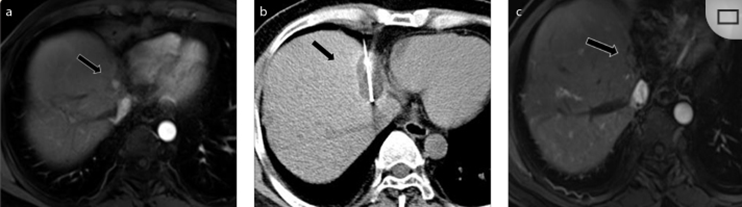

62歲女性,肝轉(zhuǎn)移(卵巢癌)腫瘤的完全消融病例

(a)軸向CT顯示病變位置毗鄰心臟和上腔靜脈(黑色箭頭)。

(b)術(shù)中軸向CT掃描:使用三個(gè)冷凍探針。

(c)冠狀面和(d)矢狀面顯示冰球毗鄰心包。

1個(gè)月后的軸向(e)和冠狀位(f)增強(qiáng)CT掃描顯示低密度區(qū)域,由于肉芽組織反應(yīng)引起的邊緣增強(qiáng)。